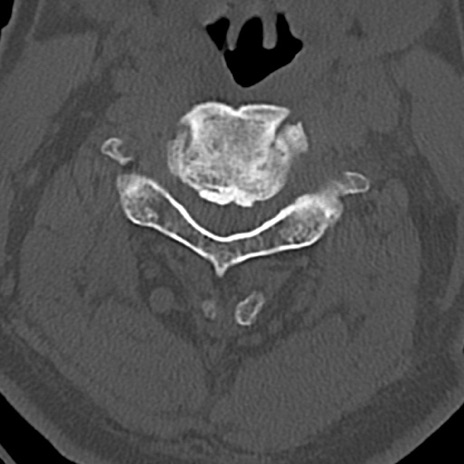

頚椎CT

横断像